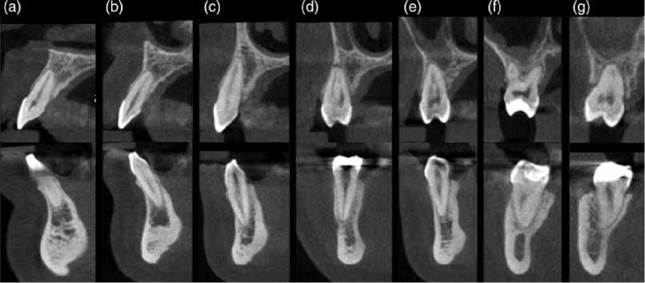

CBCT: The use of CBCT allows an exact location of the root apex. The course of the root can be followed, and deviations of the apical third of the root in all planes can be traced. The apical foramen can often be iden- tified and related to the apex of the root, especially in cases where the canal is wide. In sclerosed teeth or teeth with narrow canals, the apical foramen may not be identifiable (Figure 6.4). Resorptive processes and their effect on the shape of the root apex can often be readily appreciated [8].

CBCT: The appearance of the periodontal ligament space is similar when assessed using conventional radiography and CBCT. However, CBCT allows the periodontal ligament space to be observed in all plains and without interference caused by adjacent anatomical structures (Figures 6.6 and 6.7). Indeed there is in vitro and in vivo evidence to suggest that CBCT permits better visibility of both simulated periodontal ligament and natural periodontal ligament spaces when compared to conventional radiography [58, 98].